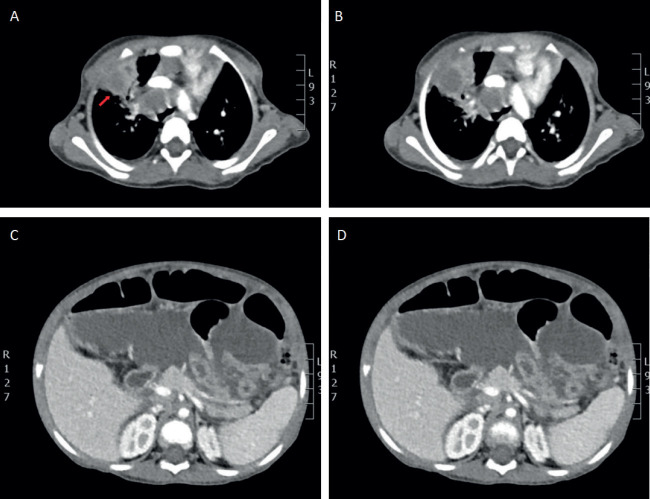

Case presentation: In children, TB often presents with a wide range of non-specific clinical and radiological manifestations, making diagnosis challenging, particularly in regions with low prevalence. We report the case of a two-year-old female with a history of constipation, weight loss, marked abdominal distension with hepatosplenomegaly, who was later diagnosed with miliary tuberculosis.

Conclusion: This case highlights an unusual presentation of miliary TB in a very young child, a demographic in which it is infrequently observed. Miliary TB remains a severe and potentially fatal condition, particularly when diagnosis and treatment are delayed. The diagnosis is usually made based on the clinical presentation, supported by a classic miliary pattern on chest X-ray.